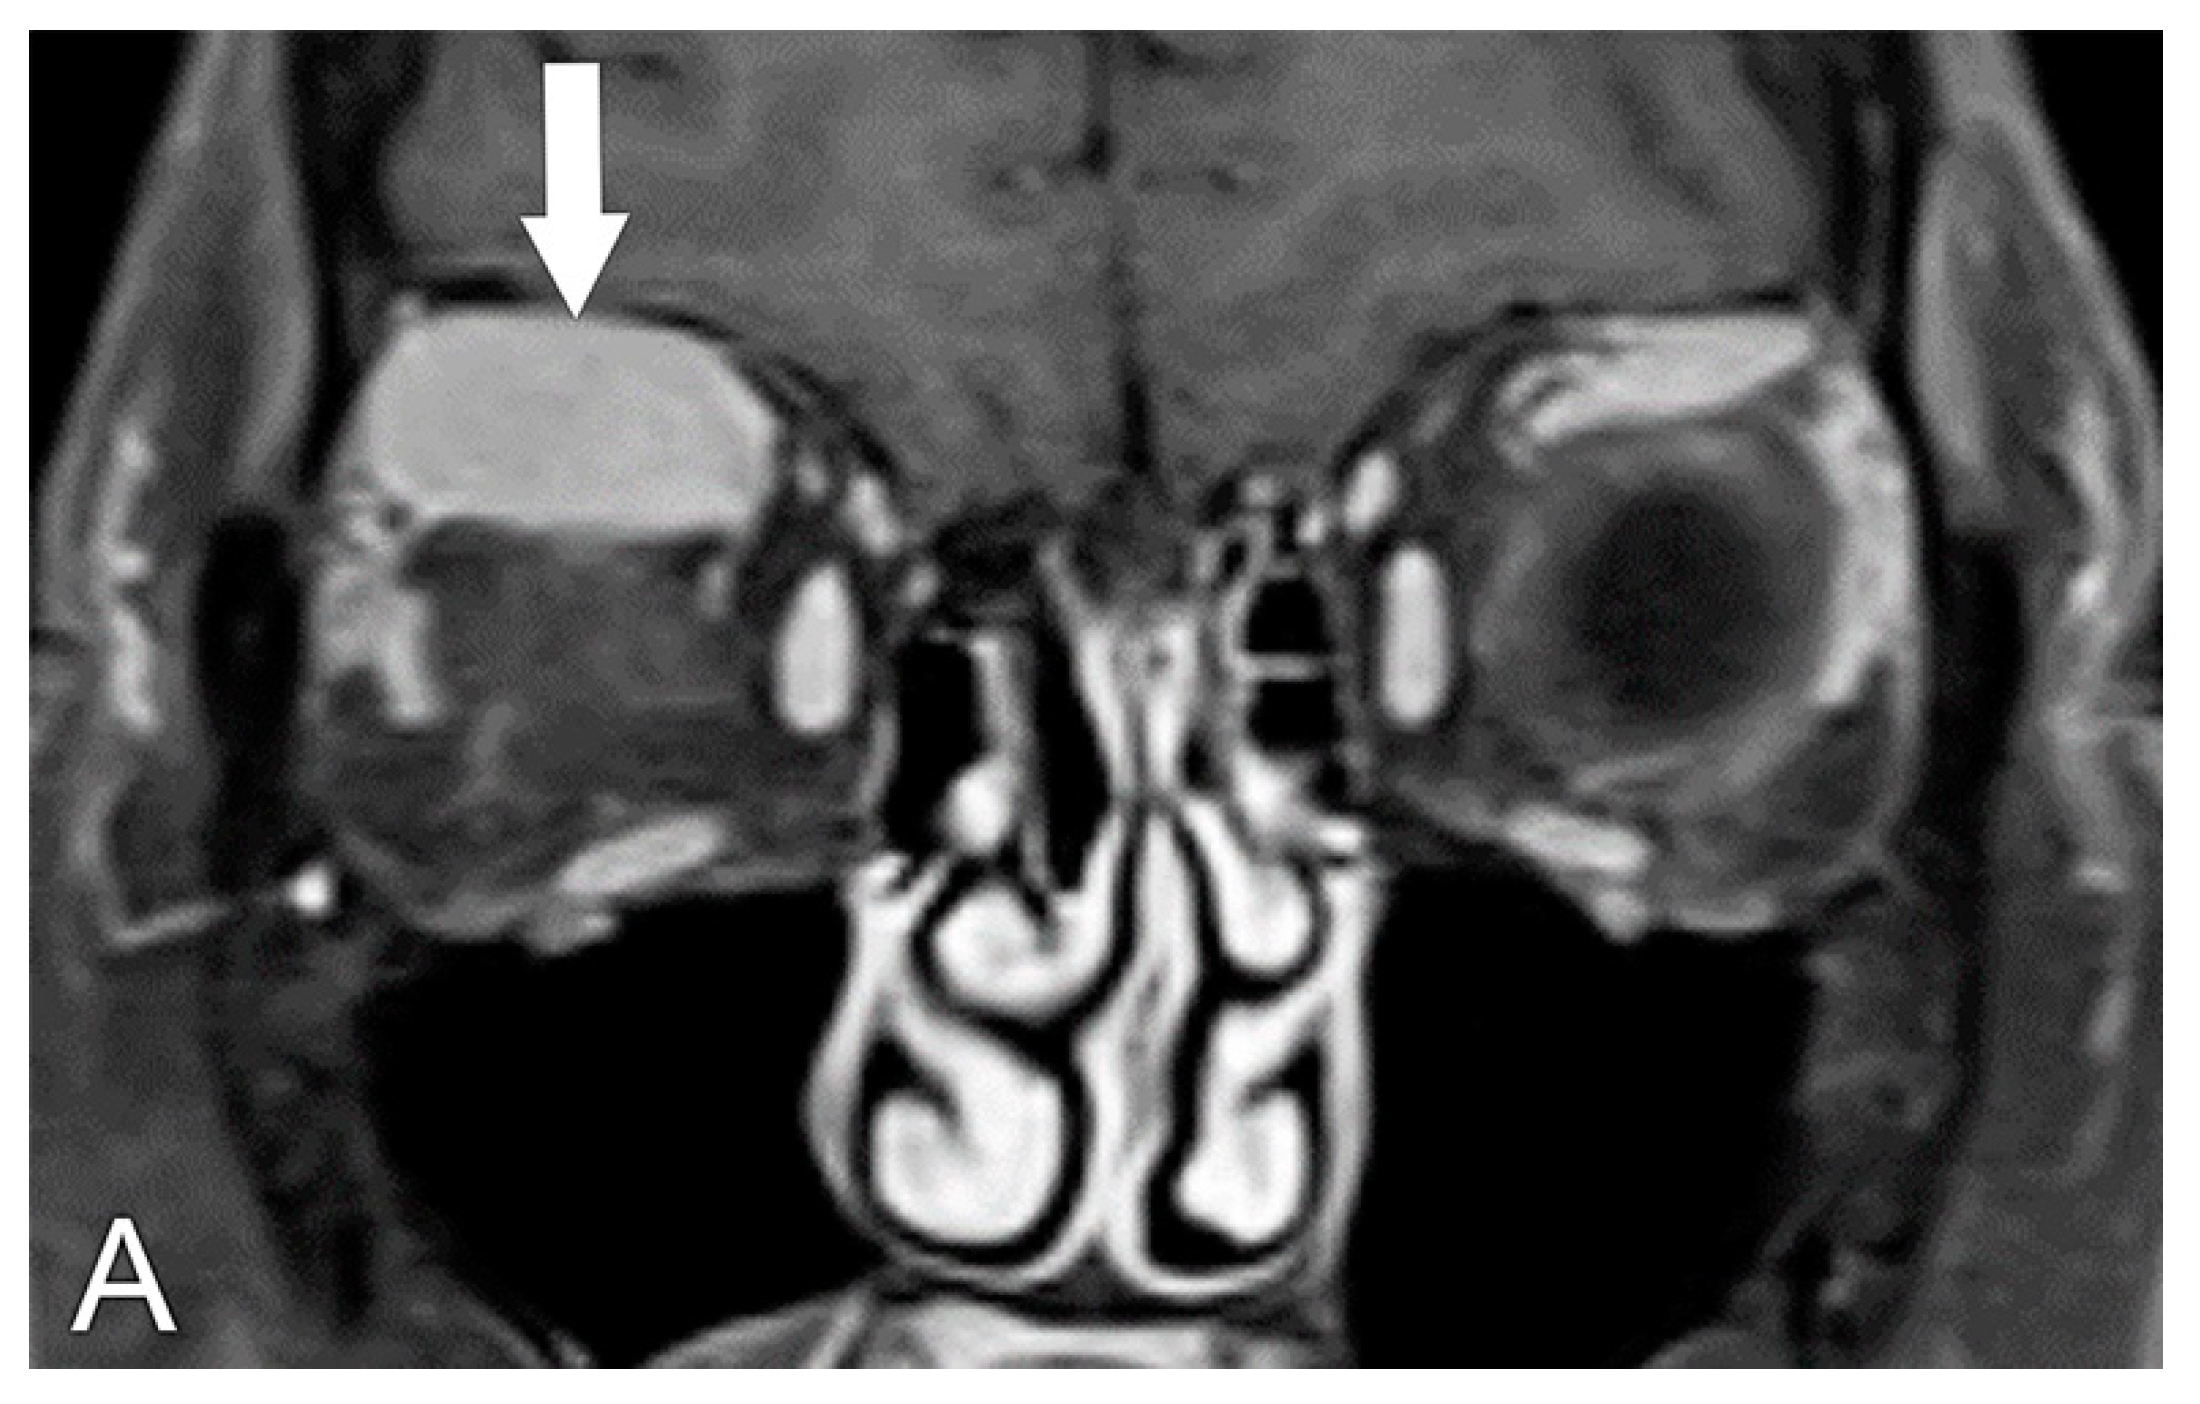

5.2. Magnetic Resonance Imaging (MRI)

5.4. Diagnosis of Compressive Optic Neuropathy (CON)

6. Radiological Differential Diagnosis